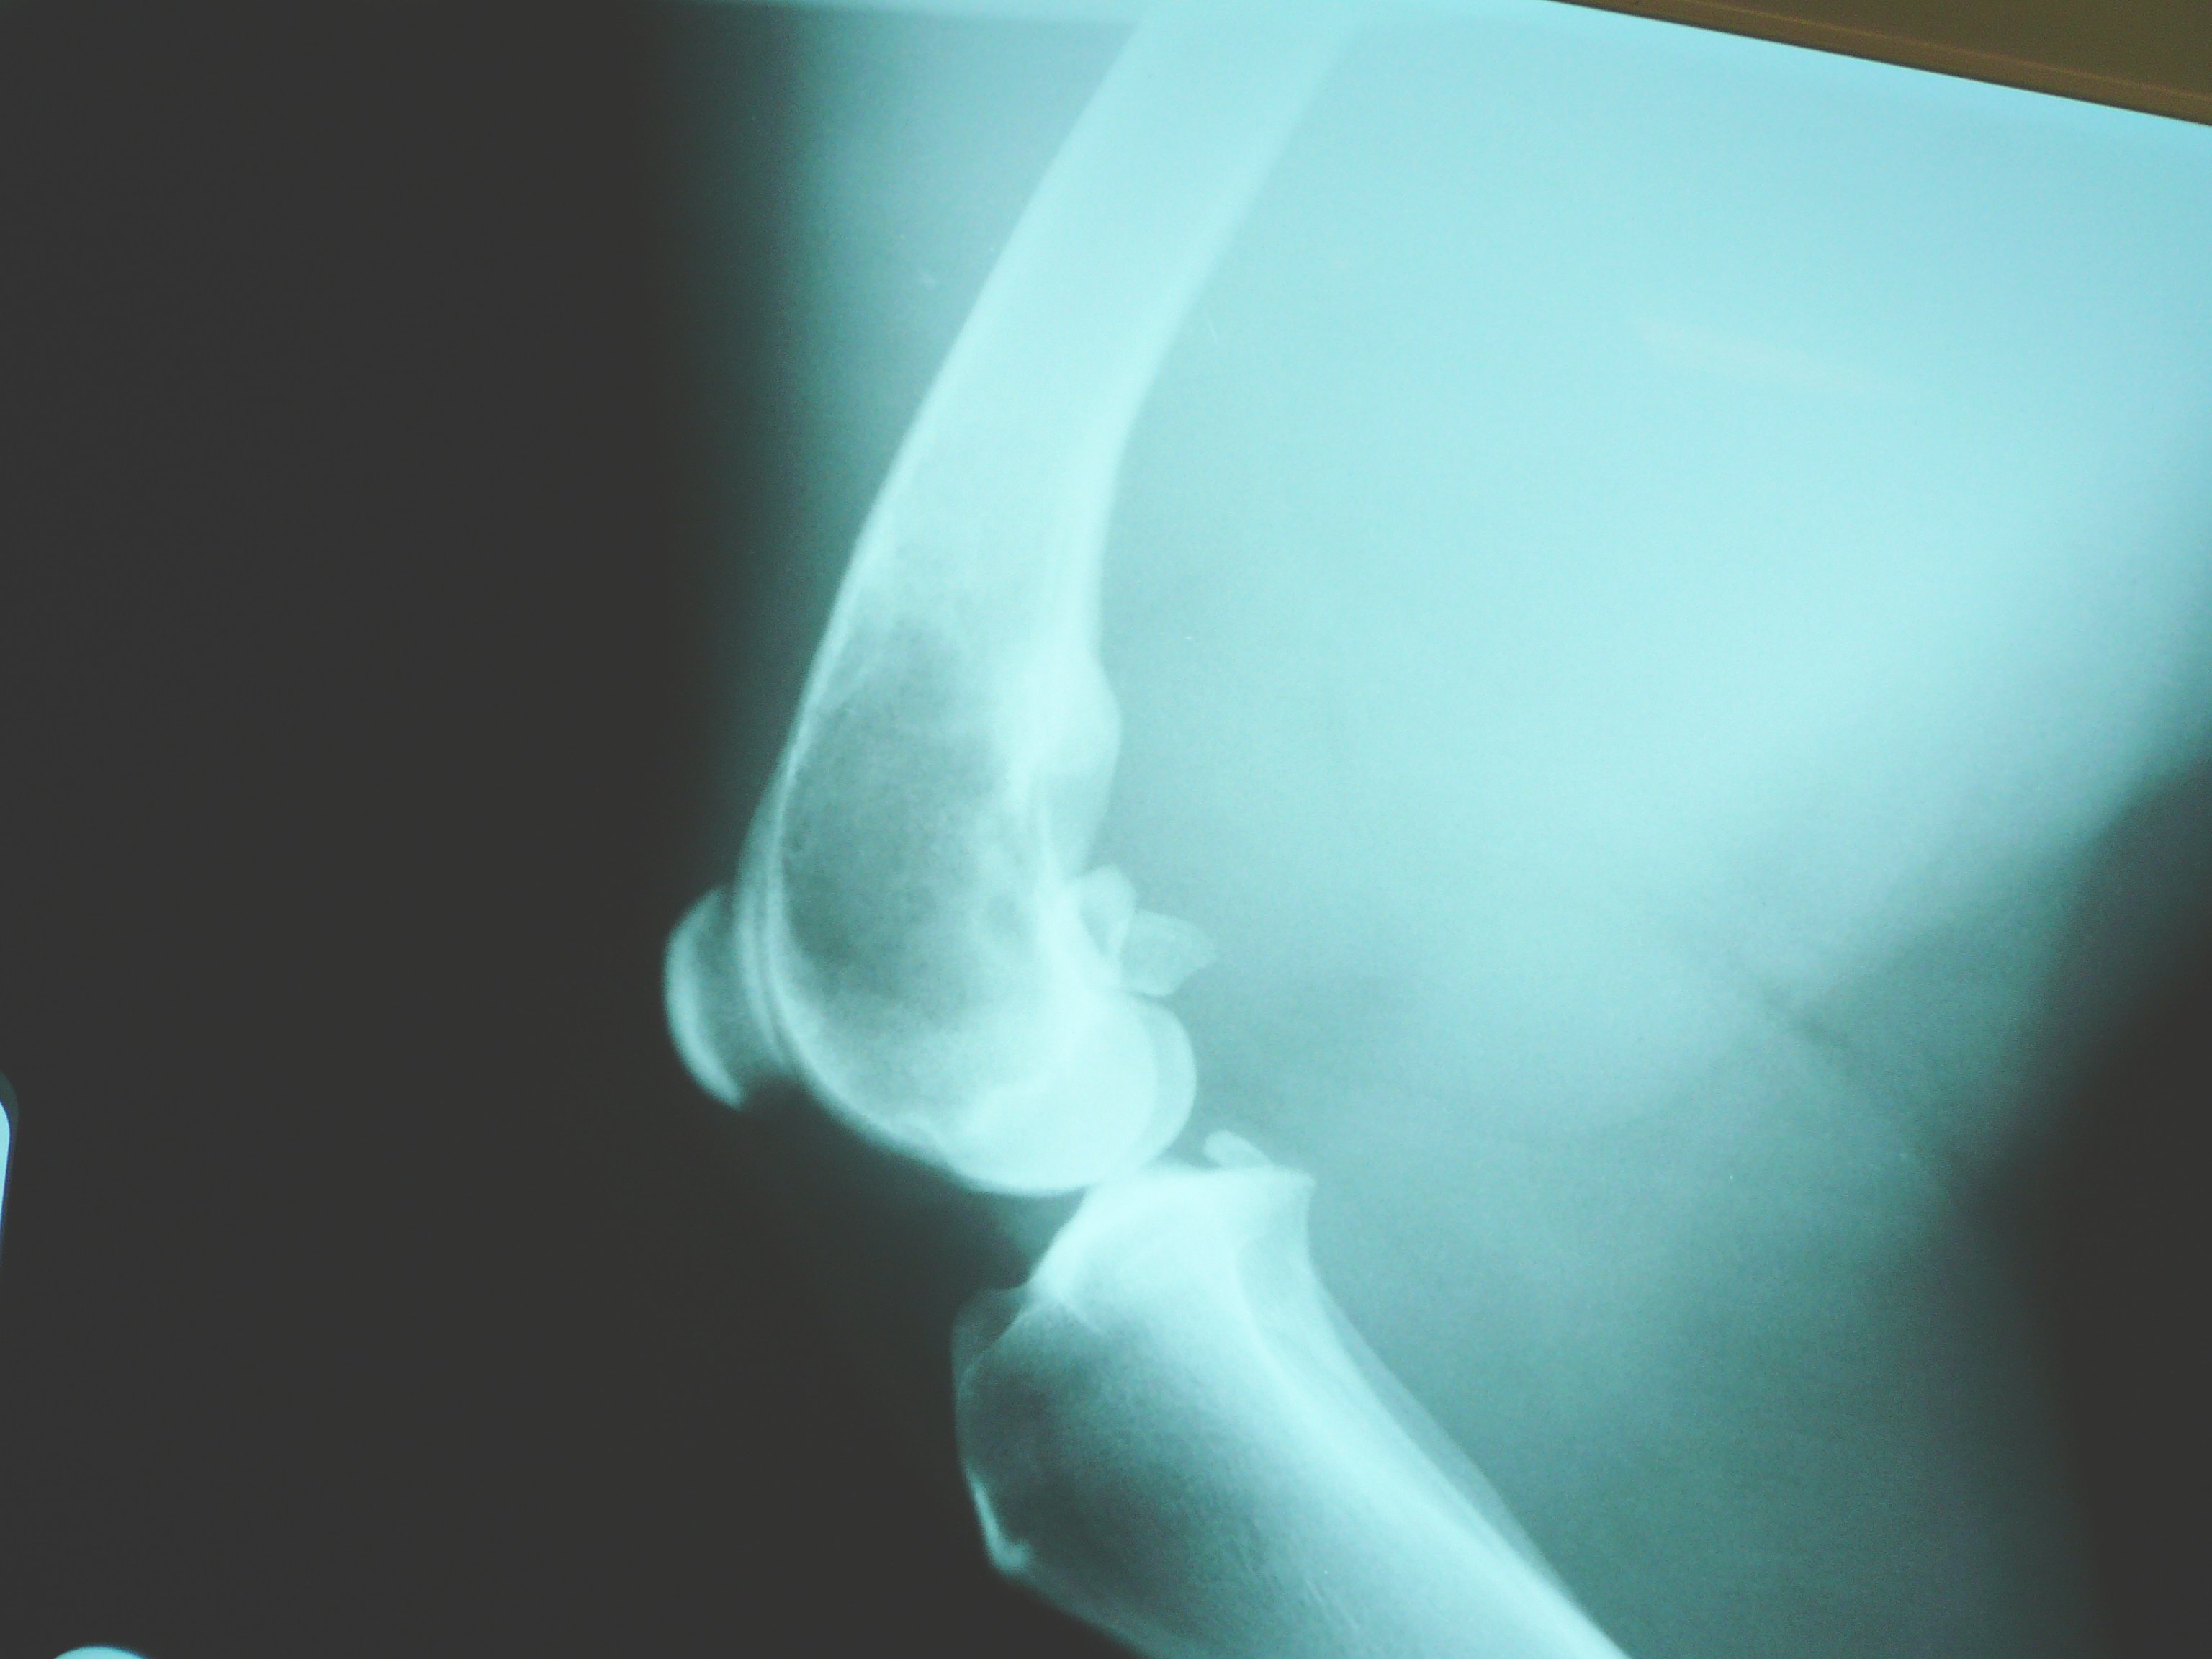

골육종은 뼈 성장이 활발한 부위에서 발생하는 경향이 있는데, 이는 성장 과정에서 골아세포가 증식하면서 세포 변형을 유발할 수 있는 돌연변이를 획득하기 쉽기 때문으로 추정된다. RB 유전자와 p53 유전자가 이러한 변형과 관련되어 있다.[70] 종양은 주로 긴 뼈의 끝부분(골간단)에 발생하며, 경골이나 상완골의 근위 끝, 또는 대퇴골의 원위 끝에 자주 발생한다. 골육종은 무릎 주변(60%), 엉덩이 주변(15%), 어깨(10%), 턱(8%) 순으로 흔하게 발생한다.[70] 종양은 단단하고 불규칙하며, 석회화된 뼈의 종양 돌기가 직각으로 방사되는 특징적인 모양을 보인다. ("전나무", "좀먹은", 또는 "태양 광선" 모양) 이러한 직각 방사 현상은 코드만 삼각형으로 알려져 있지만, 골육종을 확정적으로 진단하는 것은 아니다. 주변 조직은 일반적으로 침윤되어 있다.[70]

골육종 진단에는 엑스레이 촬영이 우선적으로 시행된다. 엑스레이 사진에서 골육종은 특징적인 "햇살 모양(sunburst appearance)"이나 코드만 삼각형(종양에 의해 새로운 뼈가 형성되는 골피질의 돌출) 소견을 보일 수 있다.[71] CT 스캔은 뼈의 해부학적 구조, 골화(새로운 뼈 물질의 생성), 연골의 석회화를 평가하는 데 유용하다. MRI는 연조직 및 골수강을 더 잘 보여준다.[71]